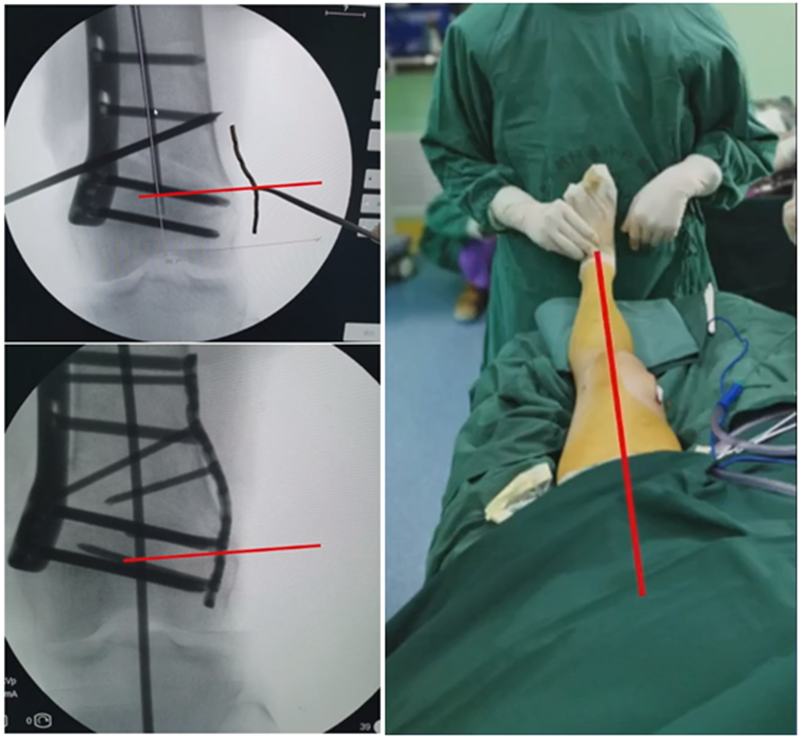

4、截骨

合页点和截骨线已确定好,按照术前计划打入导针,测量截骨深度。

注意,目前临床推荐的DFO要求最好能做双平面截骨,即还要有一条上行截骨线,上行截骨线与水平截骨线夹角大概为95° 左右。这种截骨方式一方面可以增加稳定性,同时也可以减少对上方髌股关节的干扰。

上行截骨时,要保持肢体旋转中立位,前方要有骨撬保护,由内向外完全截开,上行截骨线不存在合页。

水平截骨时,同样放肢体中立位,后侧放一把骨撬保护后方重要结构。

截骨过程中,不要求一次截骨到位,把合页深度全部截到,可以留最后一点,用钻头由前向后打出一排筛孔来,把合页端弱化,再去做闭合时就不容易折断了。

5、闭合固定

处理完后,紧密闭合截骨端。

然后核实力线,如力线位置良好,就可以采用内固定的方式将位置维持好。